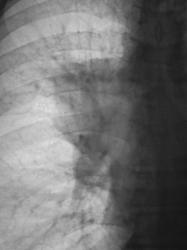

деформация правого корня. Он смещён немного вверх. Картина похоже на течение онкопроцесса.

Новообразование в области правого верхнедолевого бронха, центральная форма, ателектаз или обструктивный пневмонит в третьем сегменте, лимфангит во всей доле, расширение вехнего средостения вправо - метастазы?

Валентин Львович, а Вы не хотите сделать боковую томограмму через тень (корень) и томограмму на правый в/долевой бронх. Потому как ни одной из томограмм ни тень, ни бронхи справа не в срезе, а есть у меня такое впечатление, что имеет место периферический узел в S3, проекционно накладывающийся на тень корня, кроме того, при таком конгломерате в корне, должна быть более выражена гиповентиляция...